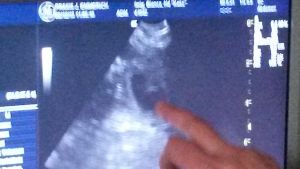

Röntgentermin beim Tierarztteam Jörn Emmerich in Vallendar 08. Januar 2014 Also ... gestern war es soweit und wir haben ein gaaaanz spezielles Bild von Keks geschossen. Zuerst war ich zwar etwas irritiert, dass das Bild mit Keks allein (ohne mich) gemacht wurde, aber der Maus ging es die ganze Zeit sehr gut und sie war auch ganz brav!!! Nach dem Bild durfte ich zur Besprechung rein. Herr Emmerich ist von Keks´ körperlichem und gesundheitlichen Zustand begeistert und er sieht keinerlei Probleme auf uns zukommen. Nichts desto trotz stehen er und Frau Dr. Häberlein nun auf Abruf bereit. ![]() Wer nun möchte, kann ja mal versuchen, die kleinen Kekskrümelchen zu zählen. Ich gebe einen Tipp: Es sind mehr als 6, aber weniger als 10. :-) Bisher ist Keks noch total entspannt, auch wenn wir am Samstag einen Fehlalarm hatten (Ihre Temperatur war schon auf 37,3 Grad). Nun wird fleißig jeden Tag Fieber gemessen und ein Protokoll geführt. Seit 2 Tagen schläft Keks in der "Keksdose" (davor in meinem Bett) und ich seit Samstag davor. Sie ist noch sehr ruhig, anhänglich und hat einen Bauch mit Beulenbildung :-) Die kleinen Kekskrümelchen kann sogar jetzt jeder sehen, der einfach Keks´Bäuchlein mal länger anschaut. Ich sage immer: Die Handballmannschaft übt das prellen :-) Da kommen auch die Gefühle der eigenen Schwangerschaft wieder hoch, wenn wir so zusammen liegen und die kleinen Krümelchen in meiner Hand sich drehen und wenden oder schon das Laufen üben ... einfach unbeschreiblich! Morgen kommen Babs, Rolf und Mini. Gästezimmer ist vorbereitet (seit Samstag :-)) und dann kann es bei Keks losgehen. Sobald wir Bilder und Info´s über die kleinen Kekskrümelchen haben, dann könnt Ihr das hier nachlesen - schneller über Facebook (wird öffentllich sein). Bis dahin bitte DAUMEN drücken! |